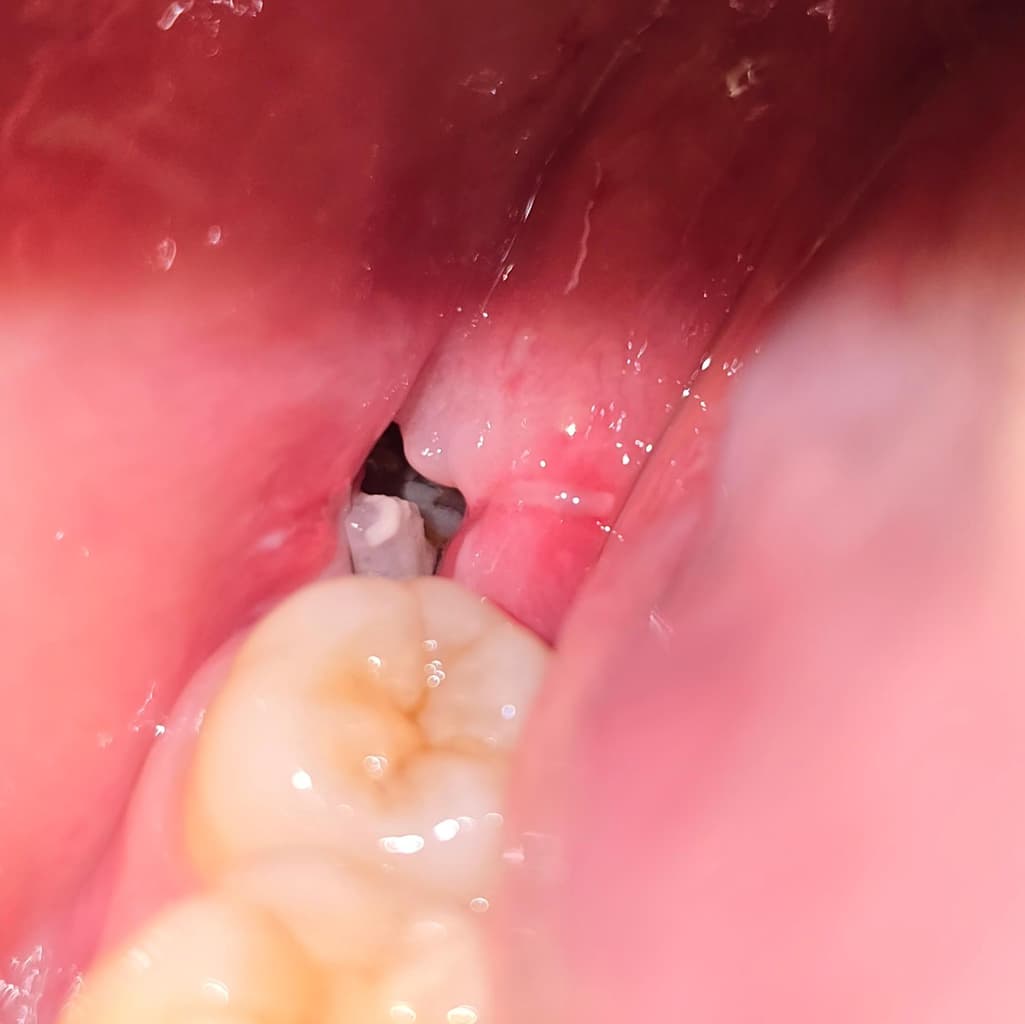

일주일 전에 사랑니 뽑고 어제 실밥도 제거했는데요 오늘 저녁 먹고 보니까 쌀알 같은 게 보여서요 가글을 해도 안 빠지고 혀로 건드리면 요리조리 움직여지기만 해요 아프거나 하지도 않고 좀 딱딱한 것 같기는 한데 단순히 쌀알이 낀 걸까요? 당장은 그냥 둬도 괜찮나요?

사랑니를 발치하고 해당 부위에 이물질이 들어가게 되면 사진처럼 보일 수 있습니다. 가볍게 가글을 하면서 빼보는 것이 좋으며 억지로 빼려고 하지 않는 것이 좋습니다. 사랑니에 있는 이물질을 억지로 빼려고 하면 출혈이 될 수 있기 때문입니다.